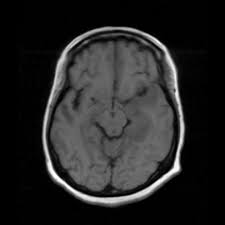

Autoimmune Encephalitis Pathophysiology And Imaging Review Of An Overlooked Diagnosis American Journal Of Neuroradiology

Autoimmune Encephalitis Pathophysiology And Imaging Review Of An Overlooked Diagnosis American Journal Of Neuroradiology from www.ajnr.org

The differential diagnoses include limbic encephalitis (paraneoplastic), gliomatosis cerebri, and status epilepticus. Ventriculitides) refers to inflammation, usually due to infection, of the ependymal lining of the cerebral ventricles. For a general discussion, and for links to other system specific manifestations, please refer to the article on coccidioidomycosis. Herpes simplex (hsv) encephalitis is the most common cause of fatal sporadic fulminant necrotising viral encephalitis and has characteristic imaging findings. Bilateral temporal lobe t2 hyperintensity refers to hyperintense signal involving the temporal lobes on t2 weighted and flair imaging. For a general discussion, and for links to other system specific manifestations, please refer to the article on hydatid disease. Given the history of fever and seizures coupled with the mri findings of bilateral mesial temporal lobe changes, herpes encephalitis requires clinical consideration. It is most often due to meningitis. Multilocularis.the larval stage is the cause of hydatid disease in humans 1. Spinal hydatid disease is an uncommon manifestation of hydatid disease, caused by the larval stage of echinococcus granulosus, or less commonly e. Terminology cerebritis is essentially the same as encephalitis except that it is used to denote brain par. It is a common finding on brain mri and a wide range of differentials should be considered 1. It is usually bilateral but asymmetrical.

The basal ganglia are usually spared. The differential diagnoses include limbic encephalitis (paraneoplastic), gliomatosis cerebri, and status epilepticus. Limbic encephalitis, mca ischaemia, tumours, effects of seizures) hyperintense t2 signal in the medial temporal lobes, inferior frontal lobes and insula basal ganglia are usually spared Hypertrophic pachymeningitis is a condition where there is localized inflammatory thickening of the dura. This patient went on to have hsv encephalitis proven on csf pcr. Twelve of 27 patients (44%, 95% ci: For a general discussion, and for links to other system specific manifestations, please refer to the article on coccidioidomycosis. Multilocularis, and describes a spectrum of disease involving the spinal cord, the spine, or both.